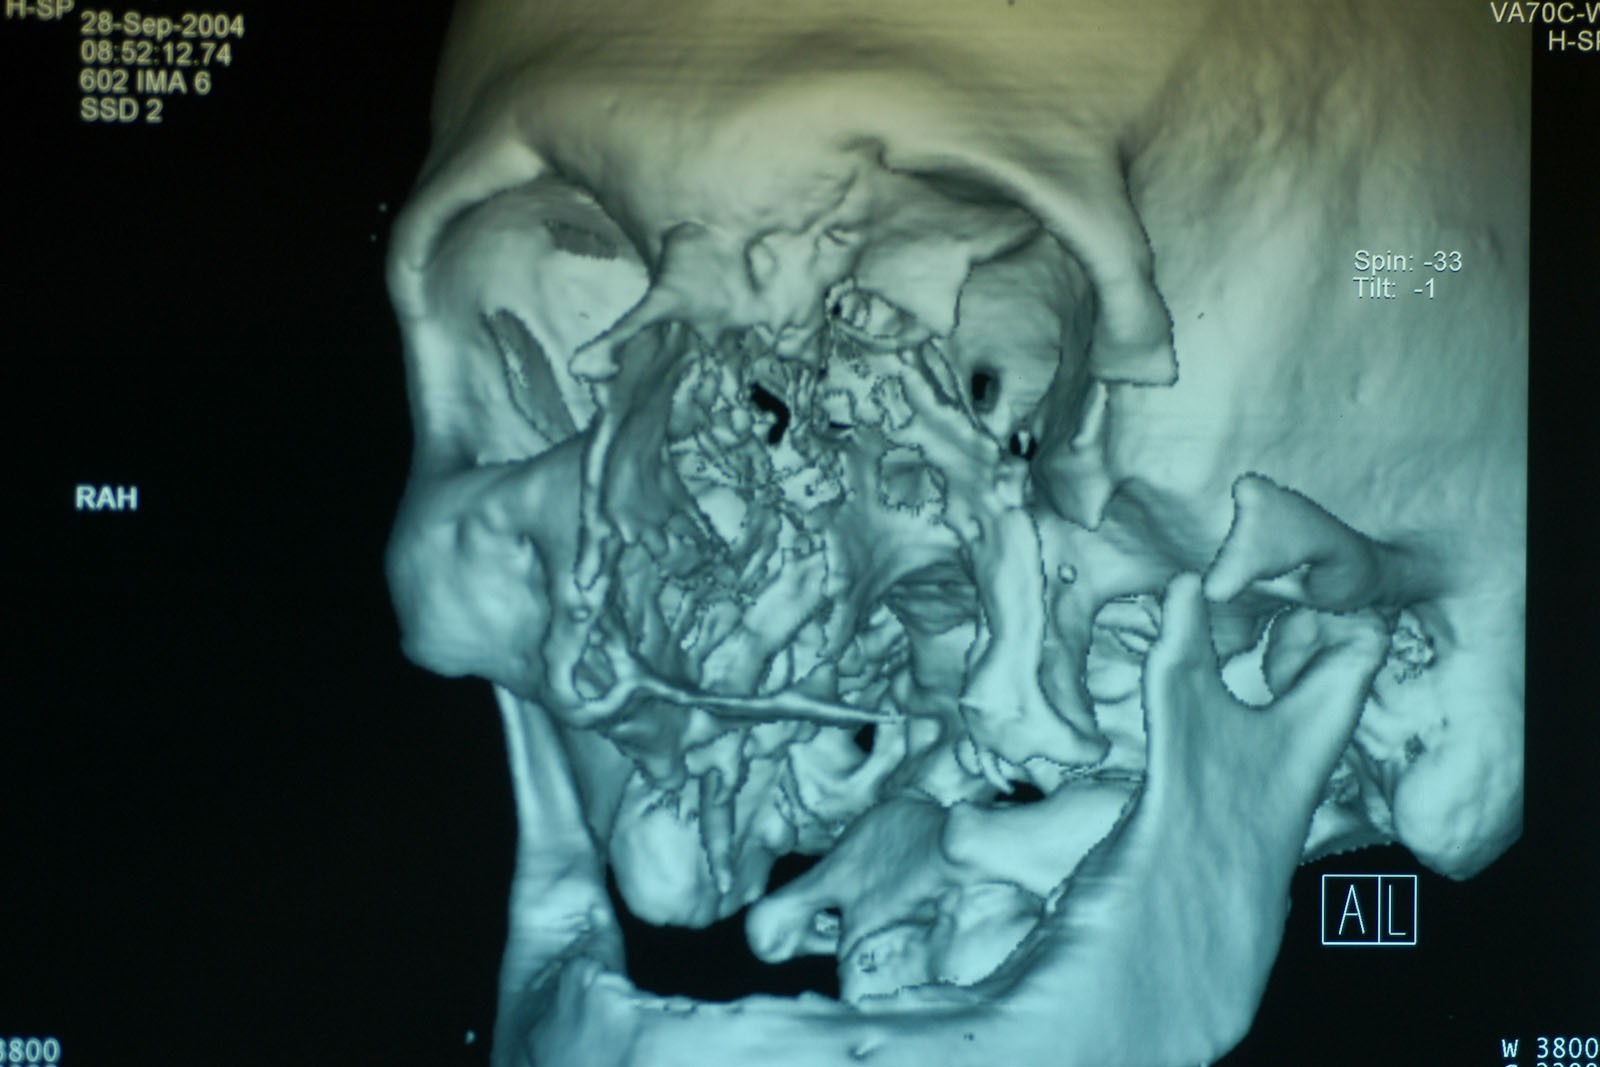

Chory po resekcji tkanek/narządów twarzoczaszki wymaga wnikliwej diagnostyki obrazującej zakres ubytku oraz stan podłoża kostnego. Wykonuje się zdjęcia radiologiczne RTG pantomograficzne szczęk OPG, konwencjonalną tomografię komputerową CT, stożkową tomografię komputerową CBCT, ukazującą trójwymiarowy obraz twarzoczaszki, oraz w razie potrzeby rezonans magnetyczny NMR. Możliwy jest również druk modeli 3D w skali 1:1 dowolnej części twarzoczaszki.

Diagnostyka ma za zadanie wykluczenie wznowy wyciętego nowotworu oraz pomoc w ocenie tkanki kostnej w okolicy ubytku. Ocena kości pozwala na zaplanowanie zabiegu wszczepienia implantów jako przyszłego fundamentu niezbędnego dla mocowania protez poresekcyjnych lub epitez twarzy.

Zastosowanie współczesnych technik obrazowania trójwymiarowego umożliwia precyzyjne zaplanowanie pozycji implantów czaszkowych, tak by ektoprotezę stabilnie osadzić na podłożu.